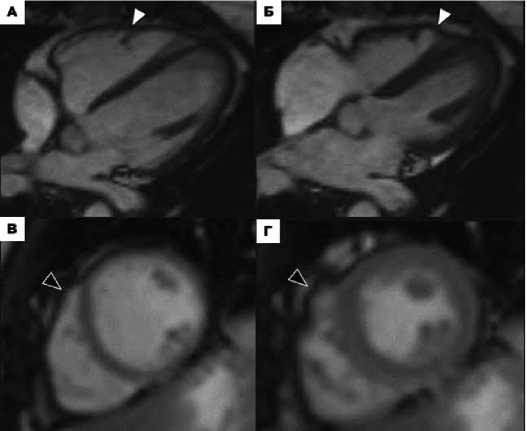

У 9 пациентов присутствовали лишь один из малых критериев АКПЖ (региональный дискинез/акинез стенки ПЖ) без очевидных структурных изменений ПЖ или дилатации ПЖ (табл. 6). Ложноположительная интерпретация регионального дискине-за/акинеза стенок ПЖ на МРТ была наиболее частой ошибкой, которая наблюдалась у данных пациентов. Так, у пациентки № 766 обнаружен дивертикул под апикальным выпячиванием ПЖ, связанный с модераторным пучком, который привел к невер- ному истолкованию регионального дискинеза стенок ПЖ (рис. региональным дискинезом стенок ПЖ на МРТ (рис. 3В-Г) при-3А-Б). У пациента № 1м с воронкообразной грудной клеткой и сутствовала частая ЖЭC и неустойчивая ЖТ.

Рисунок 3. А-Б. МРТ сердца пациента № 766. А. Кино-изображение сердца в четырёхкамерной проекции в конечно-систолическую фазу. Б. Изображение сердца в четырёхкамерной проекции в конечно-диастолическую фазу в последовательности с отсроченным контрастным усилением. Дивертикулоподобное апикальное выпячивание ПЖ, связанное анатомически с модераторным пучком – врожденный анатомический вариант (белые головки стрелок). В-Г. МРТ сердца пациента № 1м: В. Изображение сердца в темнокровной последовательности HASTE («dark blood»). Г. Изображение сердца в последовательности с отсроченным контрастным усилением. Вариант анатомии грудной клетки (Pectus excavatum) с компрессией грудиной свободной стенки ПЖ (белые головки стрелок).

Figure 3. A-Б. Cardiac MRI of patient №766. A. Cine image of the heart in the four-chamber projection in the end-systolic phase. Б. Image of the heart in the four-chamber projection in the end-diastolic phase in a sequence with delayed contrast enhancement. A diverticulum-like apical protrusion of the right ventricle, anatomically associated with the moderator bundle, is a congenital anatomical variant (white arrowheads). В-Г. Cardiac MRI of patient #1m: В. Image of the heart in a HASTE ("dark blood") sequence. Г. Image of the heart in a sequence with delayed contrast enhancement. Variant chest anatomy (pectus excavatum) with compression of the free wall of the right ventricle by the sternum (white arrowheads).

Ложноположительная интерпретация регионального дис-кинеза/акинеза стенок ПЖ на МРТ была наиболее частой ошибкой, поскольку наблюдалась у 9 (32,1%) пациентов. У 5 пациентов был явный фактор, который привел к неверному истолкованию регионального дискинеза стенок, включая перикардиальный тяж (n=3), дивертикул ПЖ (n=1), воронкообразная грудная клетка или аритмию (n=1), приводящие к артефактам.